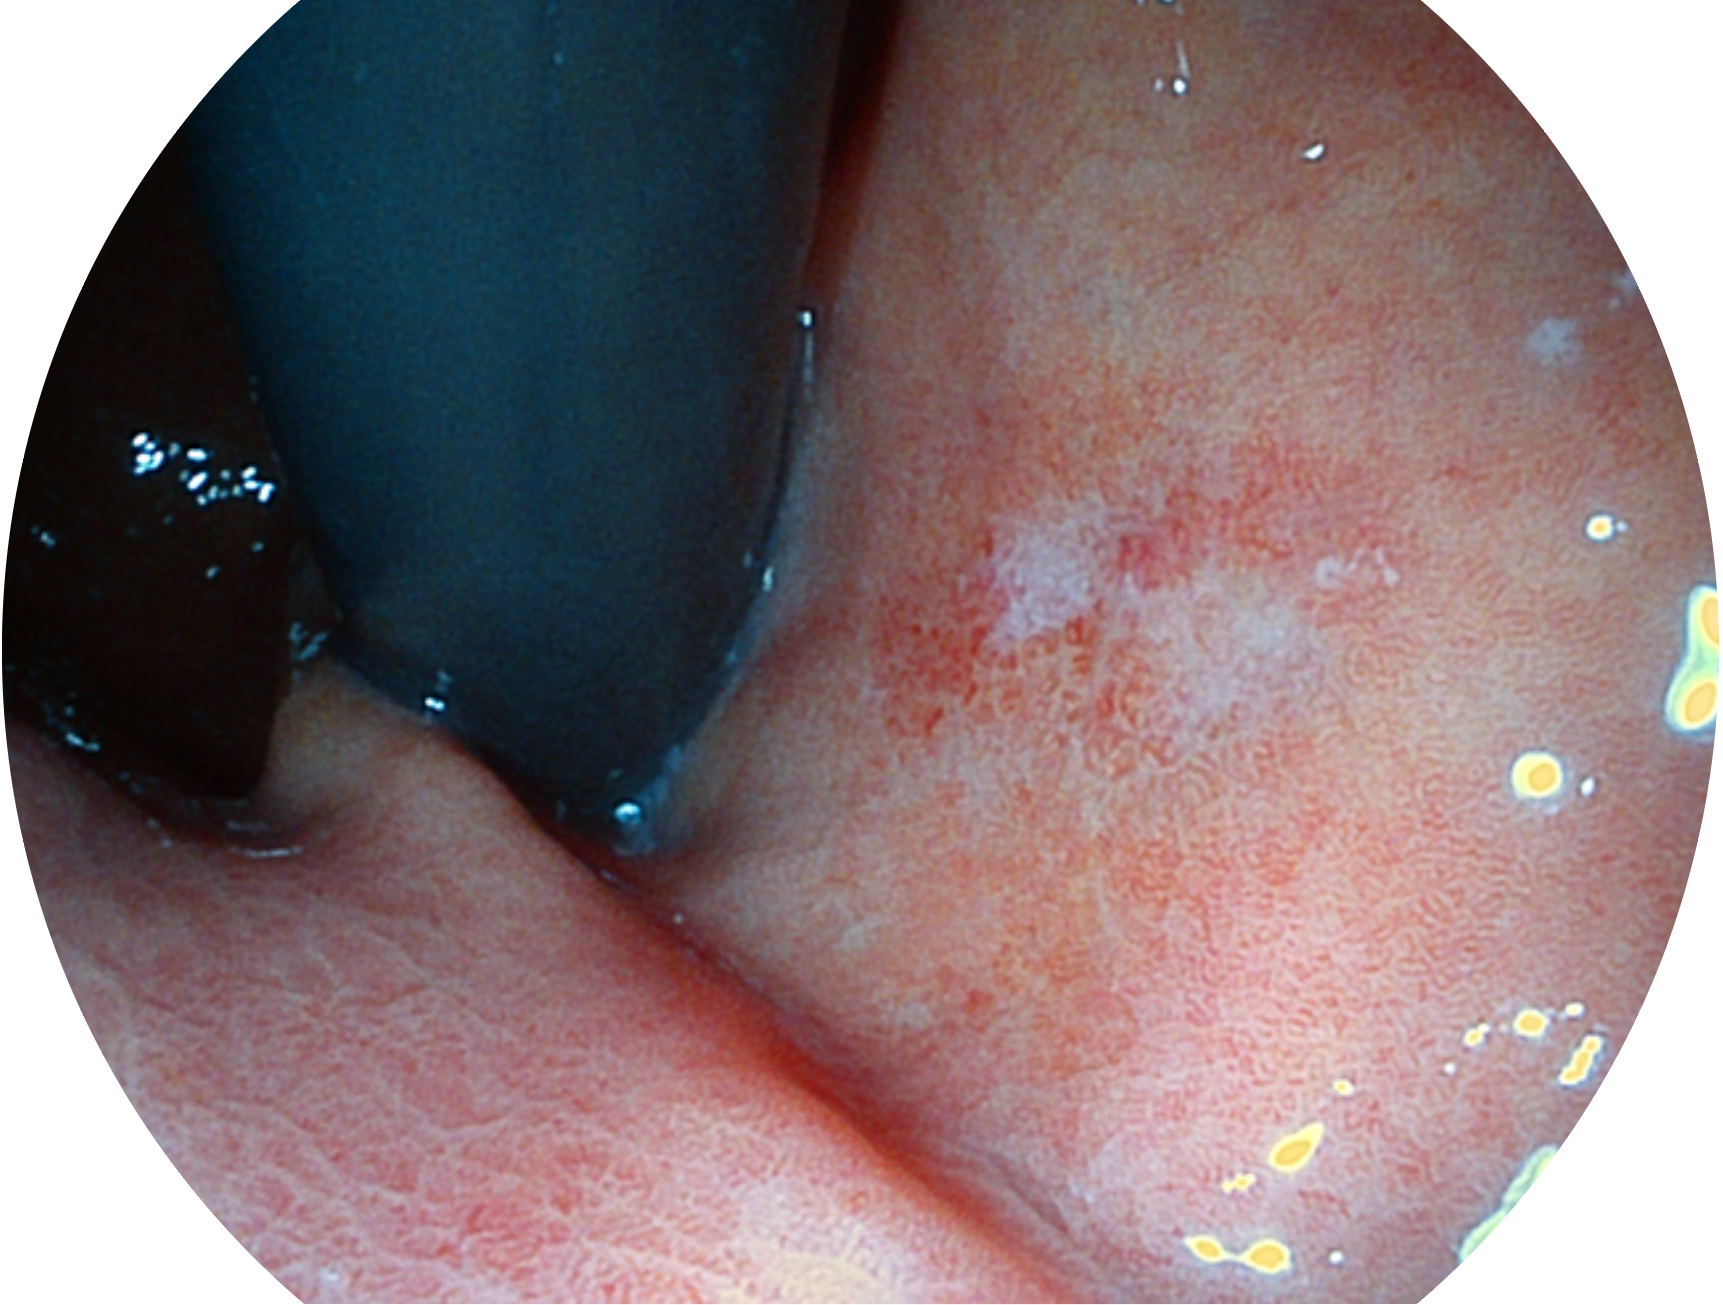

环球UG官网新开发的内镜染色技术,主要是基于多波长LED 光源的开发,VLS-55Q 四波长LED 光源是由四个不同颜色的LED光按照相应照明模式所规定的特定发光比例进行合束后形成,合束后形成的照明光的光谱由红光、绿光、蓝光及蓝紫光这四个不同的波段范围构成。具有更高光谱自由度,通过光谱比例的控制,实现了聚谱成像技术,英文全称为“Spectral Focused Imaging, SFI”,缩写为“SFI”和光电复合染色成像技术,英文全称为“Versatile Intelligent Staining Technology, VIST”,缩写为“VIST”。